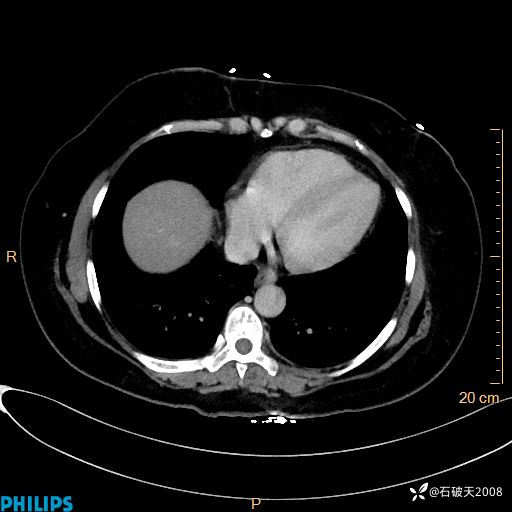

纵隔窗

静脉期